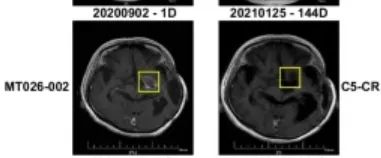

生存期大幅延长:从复发时间开始计算,患者的中位生存期达到13.1个月,12个月生存率80%,其中一名63岁的女性患者(MT026-002),复发后生存期更是达到了33.2个月,远超复发后6-8个月的中位生存期;